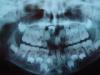

сергей76 Опубликовано 25 января, 2008 Поделиться Опубликовано 25 января, 2008 парень 7 лет,со слов мамы 2 года назад припухло прокололи получили какую то жидкость,объективно по переходной складке в проекции 11 выбухание слегка болезненное.вопрос какие мероприятия?что делать то дальше? Ссылка на комментарий

DrErix Опубликовано 25 января, 2008 Поделиться Опубликовано 25 января, 2008 парень 7 лет,со слов мамы 2 года назад припухло прокололи получили какую то жидкость,объективно по переходной складке в проекции 11 выбухание слегка болезненное.вопрос какие мероприятия?что делать то дальше? Если есть возможность, то нужно сделать трехмерную компьютерную томографию (ТКТ) верхней челюсти. Это даст возможность сориентироваться в плоскостях. На снимке вроде как не видно намеков на фолликулярную кисту. Потому если оно и вправду так, и если после ТКТ выявится, что режущий край расположен вестибулярно, предлагаете родителям подождать до 8-9 лет. Как только коронка покажется на размер, дающий возможность подклеить к ней кнопку, начинайте действовать. "...из болота тащить бегемота..." Ссылка на комментарий

Премоляр Опубликовано 25 января, 2008 Поделиться Опубликовано 25 января, 2008 да...место 11 мало...12 наклонен мезиально..Возможно такая закладка зачатка...Возможно была травма или сверхкомплектный(выяснить).Согласен с Эриксом-надо сделать томографию в 3х плоскостях...Ждать прорезывания...и смотреть..форму и возможность вытяжения... Ссылка на комментарий

МАЛЕКУЛКА Опубликовано 29 января, 2008 Поделиться Опубликовано 29 января, 2008 (изменено) Надо создавать место...в любом случае недостаток места есть...а не ждать чуда......зачаток точно расположен неправильно...или на 180 градусов или на 90...склоняюсь больше ко второму вариантус дополнительной диагностикой согласна Изменено 29 января, 2008 пользователем МАЛЕКУЛКА Ссылка на комментарий

DrErix Опубликовано 30 января, 2008 Поделиться Опубликовано 30 января, 2008 Надо создавать место...в любом случае недостаток места есть...а не ждать чуда...... зачаток точно расположен неправильно...или на 180 градусов или на 90...склоняюсь больше ко второму варианту с дополнительной диагностикой согласна В том что зачаток 11 зуба расположен неверно, понятно при первом же взгляде на ОПТГ. ТКТ предложено было сделать для решения вопроса, куда же "смотрит" коронковая часть зуба: в сторону позвоночного столба или в сторону верхней губы, т.е. положение зуба по оси Z. А создавать место в 7 лет вы чем рекомендуете? Пластинкой с винтом? Однако не забывайте, что, будучи изготовленной из твердой пластмассы она может тормознуть естественный рост челюстей по трансверзали. Потому иногда "динамическое наблюдение" бывает более полезно, чем интенсивное воздействие. И дело не в ожидании чуда, а в соблюдении старого доброго принципа "не навреди" Ссылка на комментарий

Skip Опубликовано 3 февраля, 2008 Поделиться Опубликовано 3 февраля, 2008 согласен какие нибудь варианты ещё будут? Необходимо уже приступать к активным действиям, а именно создавать место для прорезывания зубов. Дело в том, что могут возникнуть проблемы и с прорезыванием 13. Аппарат для развития челюстей можно подобрать, если Вы датите возможность взглянуть на модели и фото. Для идентификации пространственного расположения 11 необходимо дополнительно сделать внутриротовую Rg нёба и боковую ТРГ, этого будет достаточно. Теперь непосредственно в отношении дилацерации 11. Тактика, в таких случаях, не совсем однозначна и представляет, в определённом смысле, вызов ортодонту. Я почти уверен, что коронка зуба развёрнута на 180 гр. и, в данном случае, прибегнул бы к хирургической репозиции или, как ещё называют, трансальвеолярной трансплантации. Если Вы об этом не слышали, то другими словами, подойдя хирургическим путём к зубу, развернул бы зуб в нужное направление, создав таким образом условия для его правильного формирования. Если говорить об ортодонтическом "вытягивании" резца, то по моим наблюдениям, лучшие результаты показывают зубы с вестибулярным отклонением от 45 до 90 гр. C похожим на "Ваш" случай, я сталкивался только однажды и всё прошло успешно, причём оперировал собственноручно ( ...очень помогли рекомендации из "Atlas of replantation and transplantation of teeth" Andreasen JO.) Ссылка на комментарий

Skip Опубликовано 25 марта, 2008 Поделиться Опубликовано 25 марта, 2008 вот кт всё заархивировано думаю ни чего сложного прога там же,каковы будут тактики лечения?МАЛЕКУЛКА была права, зубик повёрнут чуть больше 90*, значит можно вытянуть, создав предварительно место. Формирование корня, как мне показалось, чуть меньше 1/2. И еще, у парня серьёзные проблемы, а именно, на одной из сторон ветвь н.чел и, соответственно, мыщелковый отросток, сдерживаются в росте (на срезах хорошо видно), т.к. черепок деформирован (родовая травма), ну и прикус соответственно. Ссылка на комментарий

Orthodoc Опубликовано 27 марта, 2008 Поделиться Опубликовано 27 марта, 2008 вот кт всё заархивировано думаю ни чего сложного прога там же,каковы будут тактики лечения?Зубик лежит перпендикулярно тому как должен лежать. Очень сомневаюсь, что прорежится самостоятельно. Попытаться поставить на место можно, но в более старшем возрасте, лет в 11-12, когда прорежутся зубы и можно будет создать опору для вытягивания. У мальчика скорее всего формируется перекрестный прикус (выложите фото), на данном этапе нужно бороться с этой проблемой. Каким способом, смогу ответить после того, как увижу фото. При плохом стечении обстоятельств - удаление ретенированного резца после 12 лет, создание оптимального места для протезирования и окончательная коррекция прикуса на брекет-системе. Жду фото в окклюзии право, лево,фронт, лицо с сомкнутыми губами. Ссылка на комментарий